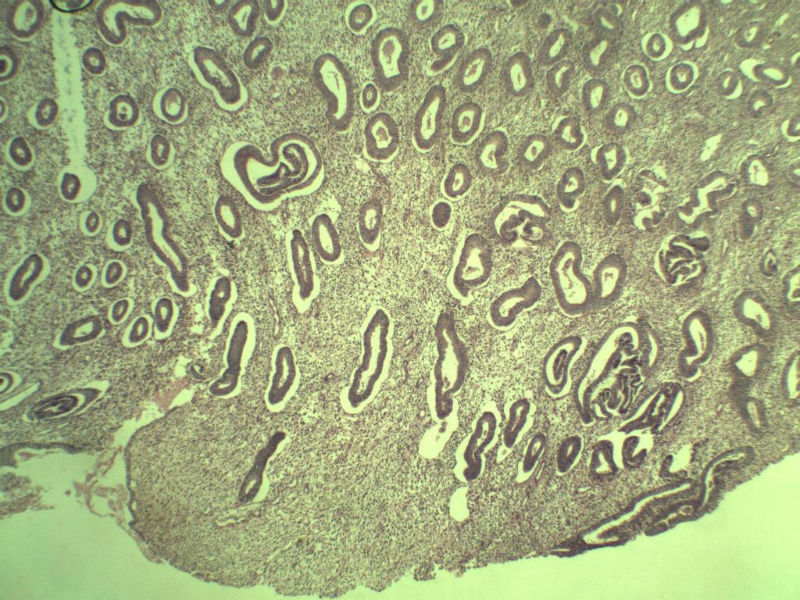

42岁 月经不规则一年 b超发现子宫肌瘤 行全子宫切除术  我取材时发现子宫颈管上段有一质地较硬区 2*1cm  请各位老师看看 是子宫内膜癌不? 谢谢了!

这是子宫颈管上段

子宫颈管上段图1

非癌,考虑子宫内膜异位症或腺肌瘤

肌层内腺体的特点:1、无内膜间质。

2、有鳞化。

3、无异型。所以应该还是个良性病变

非典型性息肉样腺肌瘤。

诊断依据:

1.临床特征:主要发生在绝经前女性,中位年龄39岁,大多数伴有月经紊乱。

2.大体特征:最常见于子宫下段,平均大小为直径2cm,表现为圆形,凸出于表面。息肉样的本质不总是很明显,也有无蒂和广基的肿瘤。

3.镜下特征:上皮成分由杂乱无章排列的不规则的子宫内膜型腺体构成,可以是立方形到矮柱状或假复层。显示有广泛的鳞化区域(本例图11-17均显示鳞化),表现为圆形的“桑葚”(图16-17);间质主要由平滑肌构成,且混有纤维组织。